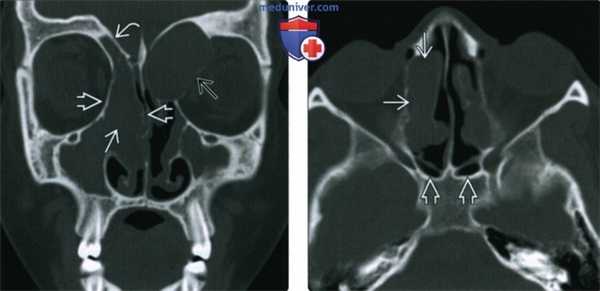

(Слева) При корональной «костной» КТ у девочки 14 лет с муковисцидозом (МВ) определяются типичные признаки ПНП, в т.ч. снижение пневматизации ячеек решетчатой кости справа за счет полиповидного материала, распространяющегося также в полость носа, и доброкачественное ремоделирование костей. Обратите внимание на большое мукоцеле решетчатой кости слева с распространением в орбиту и гипоплазию правой лобной пазухи.

(Справа)При аксиальной «костной» КТ у пациента с МВ визуализируется крупный полип в полости носа справа, связанный со средней носовой раковиной. Выраженная гипоплазия основных пазух часто наблюдается при МВ.

(Слева) При аксиальной КТ без КУ визуализируется большой полип, заполняющий полость носа справа, и выбухающий из правой ноздри. Обратите внимание на доброкачественное ремоделирование костей и смещение влево костной носовой перегородки. Уровни «жидкость-газ» с пузырьками газа в верхнечелюстных пазухах неспецифичны и могут быть обусловлены воспалительным компонентом при остром синусите.

(Справа) При аксиальной MPT Т2ВИ у пациента с тяжелым полипозом визуализируются множественные гиперинтенсивные полипы, заполняющие полость носа и внутренние отделы верхнечелюстных пазух.